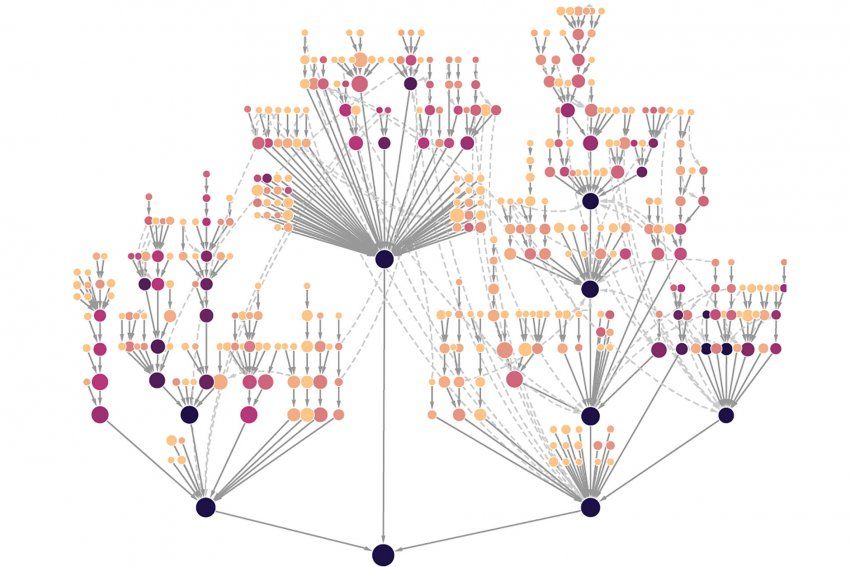

“We’re elevating the conversation about cancer from individual genes to proteins, allowing us to look at how the varying mutations we see in patients can have the same effects on protein function,” said Ideker, noting that this work represents new technological capacity to explain the effects mutations in a more precise way. “We’ve produced the first map looking at cancer through the lens of interactions between proteins.”

The effort to map these effects, dubbed Cancer Cell Map Initiative (CCMI), is revealing, on a monumental scale, genetic patterns and organizing principles that underlie the disease and potential new ways to tackle it.

CCMI’s goal was to map the constellation of protein complexes formed by about 60 genes commonly involved in either breast cancer or cancers of the head and neck, and to see what each looked like in healthy cells. Alongside that effort, he created maps of how protein complexes are affected by hundreds of gene mutations in two cancerous cell lines.

Doing so presented a formidable computational challenge. The CCMI collaboration allowed the team to use advanced and novel data analysis to reveal not only whether the mutation affected interactions between proteins, but to what extent.

Each node represents a protein system carrying out cellular functions such as mobility or immune signaling. Nodes farther out on the branches represent systems with few proteins and highly specialized processes, while those closer to the root have many proteins and correspond to generalized processes. Darker colored systems, and their subsystems, are under selection in more tumor types. Image by Krogan lab